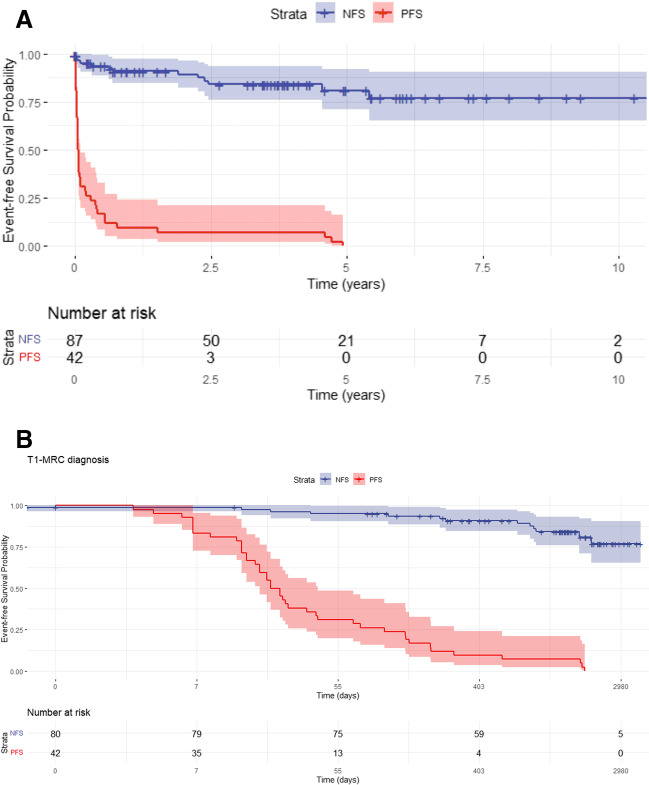

The Kaplan–Meier curve for event-free patient survival showed a markedly higher probability of event occurrence over time with PFS vs. the normal-excretion patients. The difference was especially visible in the first year post-MRI, which was better seen after log-conversion of the x-axis (p < 0.001) (Fig. 5A, B).

Univariate Cox regression showed that the risk of event occurrence, including death and OLT, rises ~ 19-fold annually for PFS patients [95% CI, 9.9–38.2]. However, HR was only 1.9 for HGS [95% CI, 1.4–2.6] and 2.1 for DS [95% CI, 1.2–4.0] based on T2-MRCP diagnosis. Clinical scores were included in the multivariate analysis to achieve the best fit. The PFS and AOM were identified as independent risk factors with HRs of 28.6 [95% CI, 12.5–65.5] and 1.6 [95% CI, 1.0 – 2.5], respectively (Table 4).

The Kaplan–Meier curves showed a clear separation between adverse clinical events in T1-MRC NFS vs. PFS subpopulations. Furthermore, multivariate analyses using Cox regression showed that T1-MRC-based diagnosis was an independent risk factor for adverse events in PSC patients, outperforming lab tests and clinical scores, even after categorization into an ordinal system. In addition, except for T1-MRC, no other MR metric correlated with established clinical scores, which was unsurprising, as we know T2-MRCP-DS/HGS-diagnosed patients range from asymptomatic to having abnormal liver function tests and/or cholestasis [ref. 4].